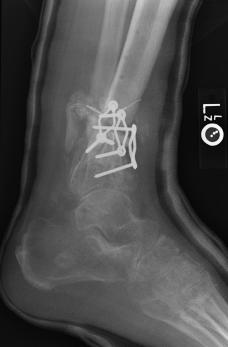

Post-skin graft & bone infuse surgery X-Rays of the left & right ankle

These x-rays were taken four weeks after surgery where grafts of skin were used to cover the open wound on Liam's left ankle. Dr. Gottlieb

infused bone material into the tibia gap of the left ankle. The 3 cm fragment in the left ankle does not appear to have fused or to be

obstructing normal movement so no immediate plans exist to modify the remaining bone fragments. Following these x-rays it is the plan to

remove the right ankle screw that was misplaced by Dr. Keller.